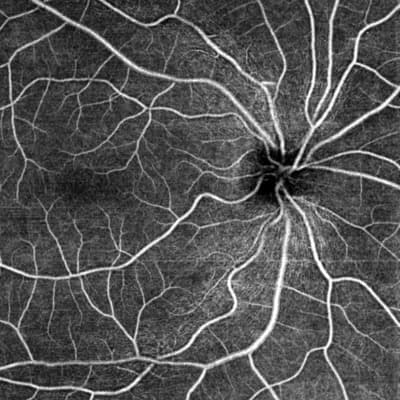

Survey - OCT Anomaly Detection Methodology – Seeking Experts in Singapore

Seeking validation on OCTA anomaly detection.